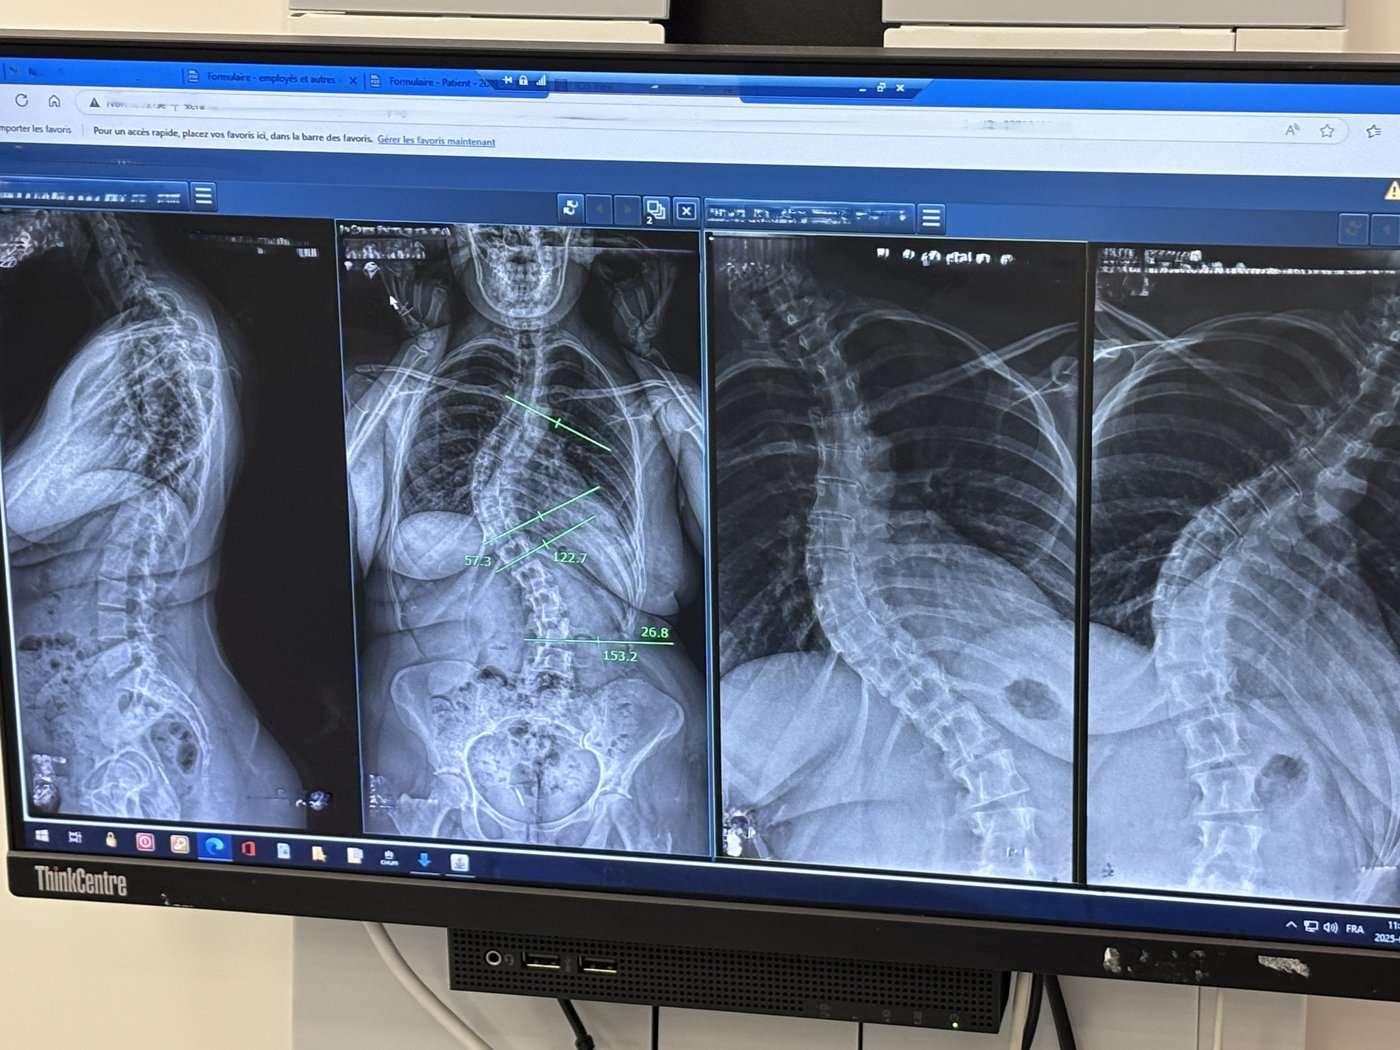

MONTRÉAL — Le dépistage de la scoliose chez les enfants présente des lacunes au Québec, déplore un spécialiste, ce qui signifie que plusieurs sont vus tellement tardivement que seule l'option chirurgicale est alors disponible.

«Il y a un rebond du nombre de patients, et les enfants se présentent trop tard», a résumé le docteur Jean Ouellet, qui est chirurgien orthopédiste à l’Hôpital de Montréal pour enfants.

On sait maintenant que c'est faux, a dit le docteur Ouellet: si le problème est détecté assez tôt et si des mesures correctives sont mises en place, trois enfants sur quatre échapperont au bistouri.

«Environ 40 % des patients qu'on voit n'ont pas de scoliose, a dit le docteur Ouellet. Mais pour 30 % de ceux qu'on voit, il est déjà trop tard et on peut seulement leur offrir une chirurgie. Donc on est inondés de patients qui n'ont pas réellement une scoliose, pendant que les patients qui ont un besoin aigu ne sont pas vus. J'aime mieux voir plus de patients et les rassurer, mais il faut trouver un juste milieu.»